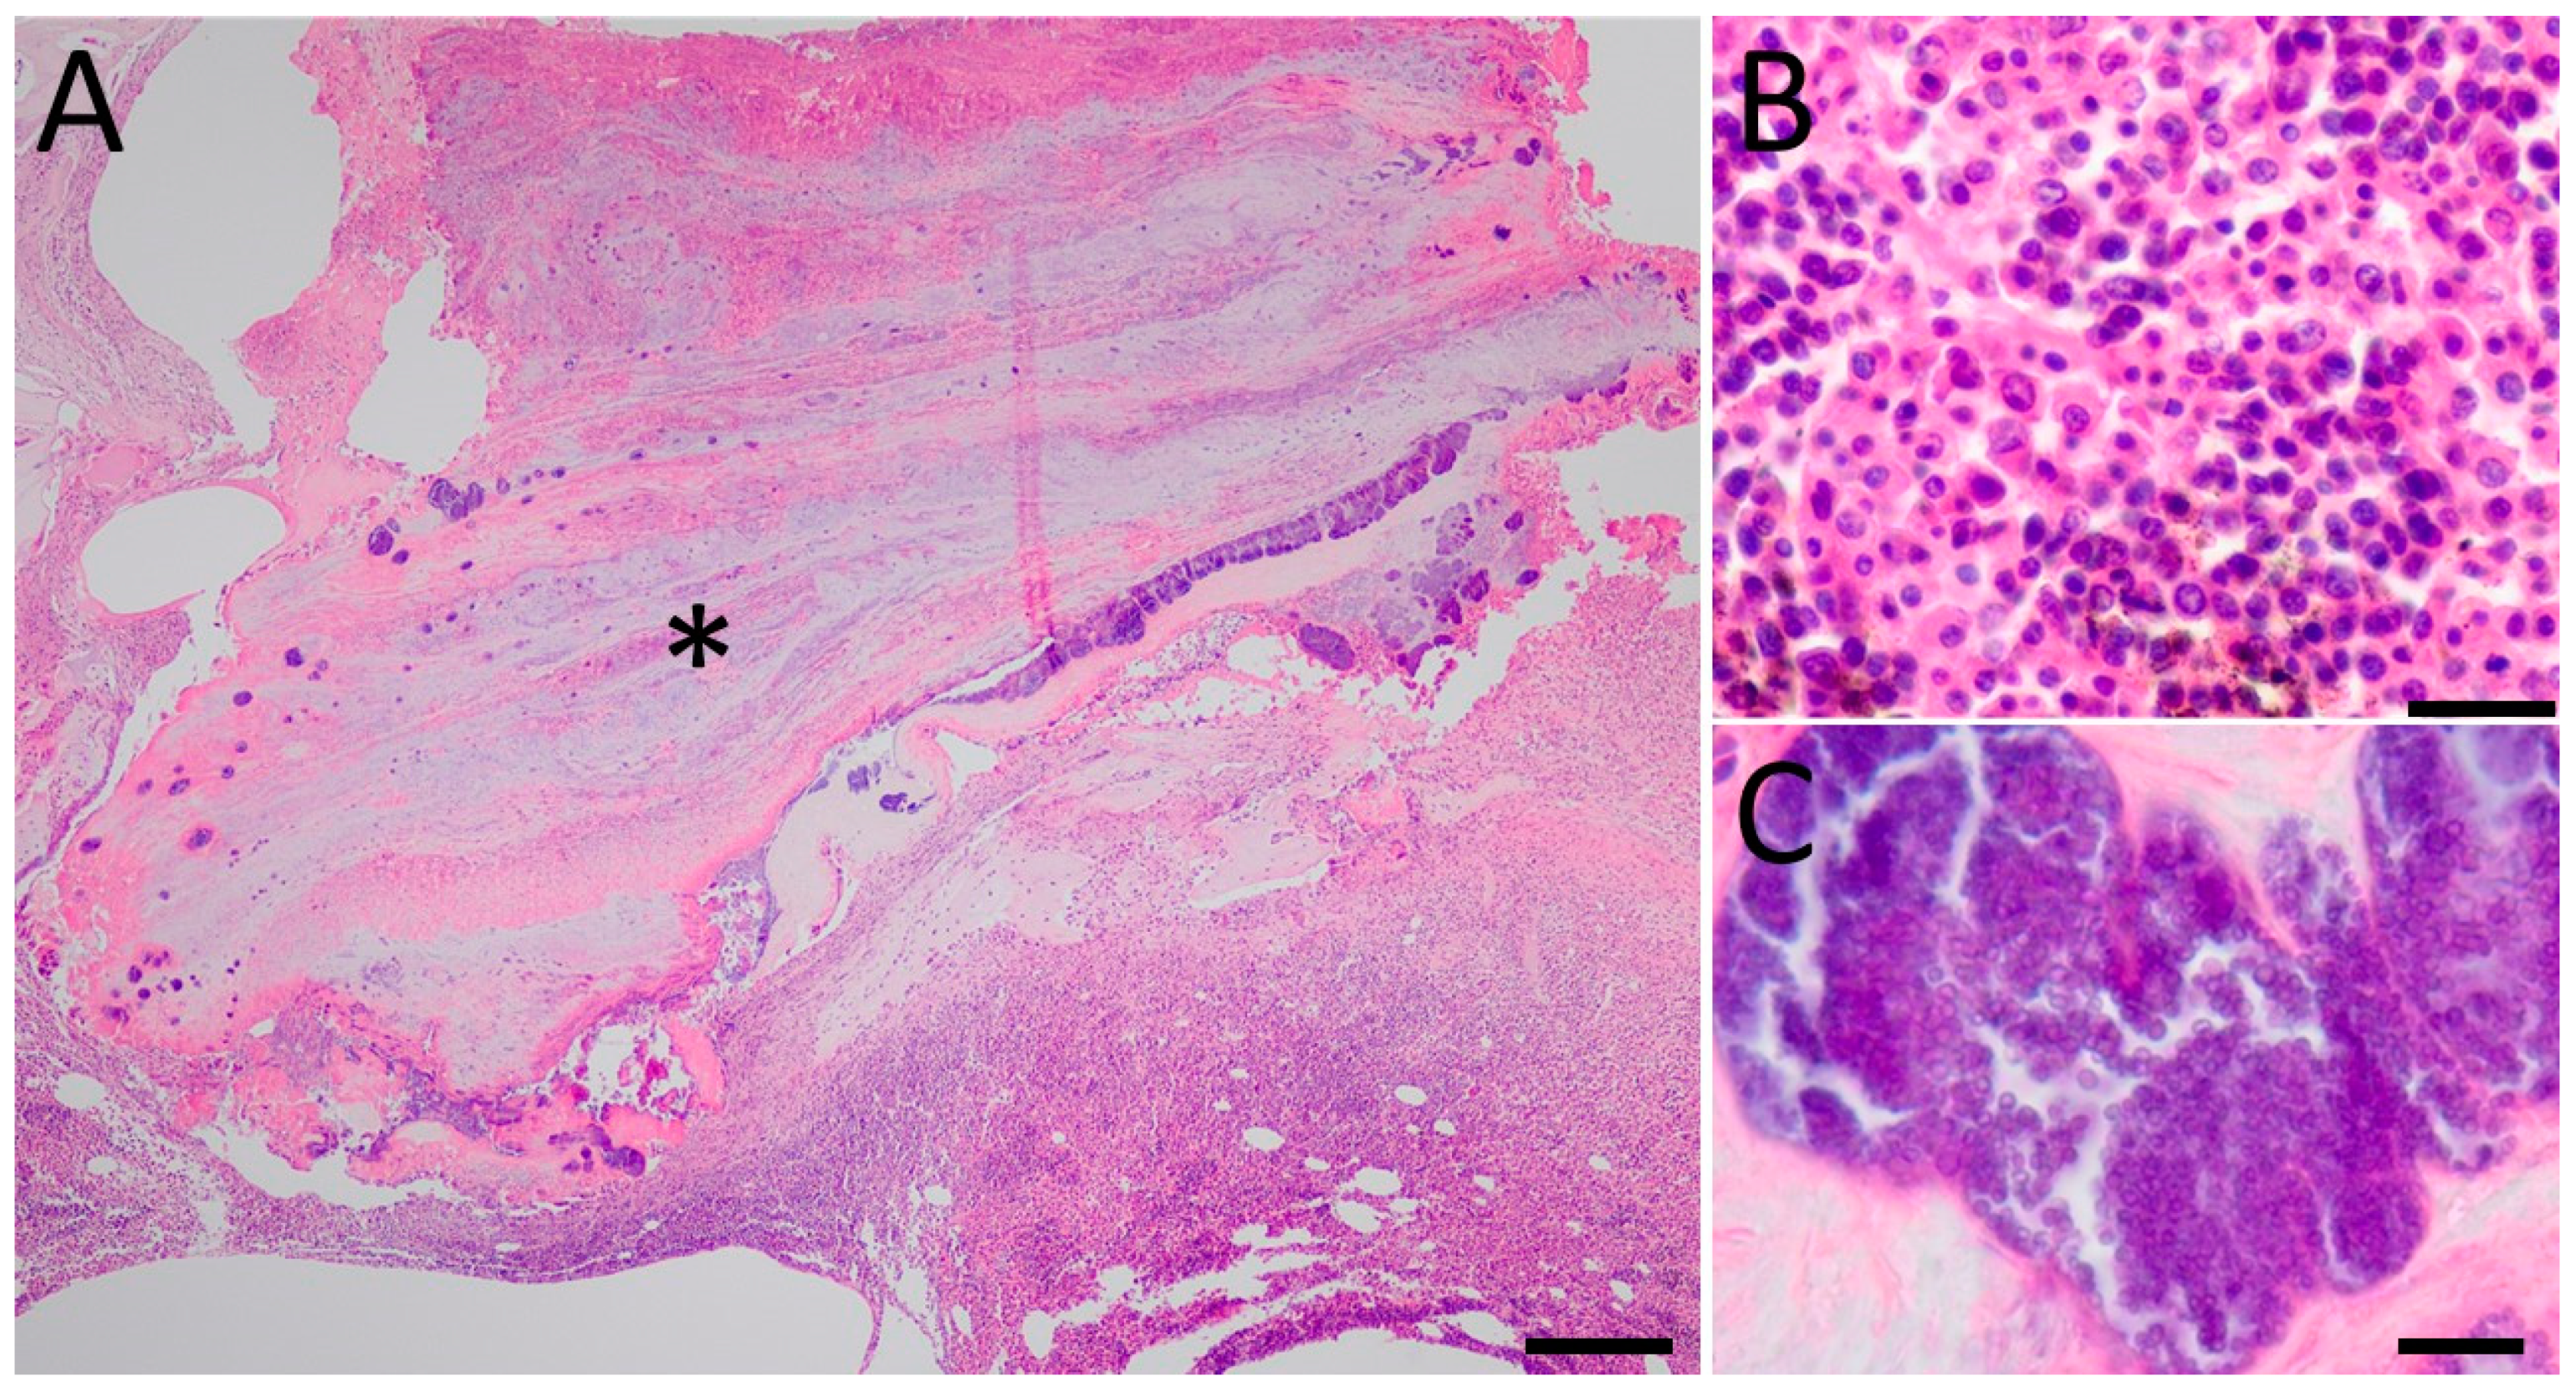

3.2. Histology